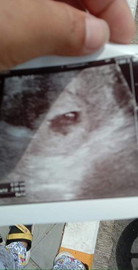

กำลังจะมีลูก